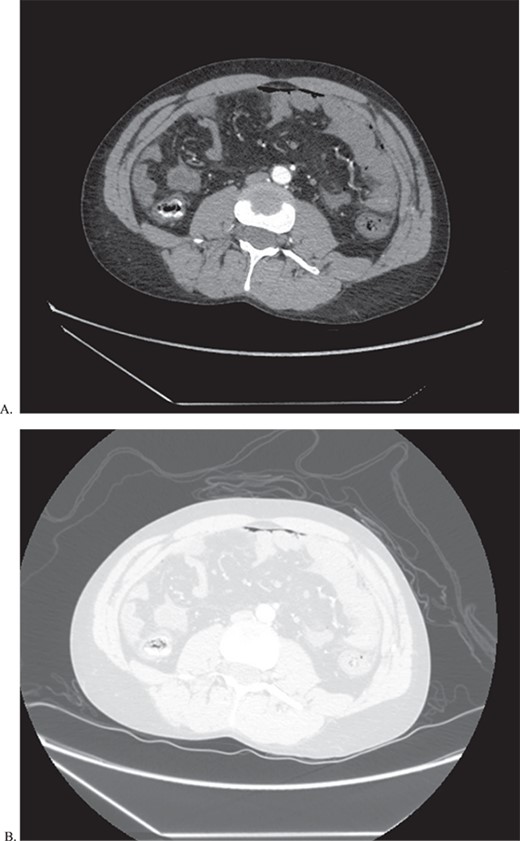

He returned to the ED on POD 9 with episodes of emesis and abdominal pain. En route, he was hypotensive and had a coughing spell with witnessed evisceration. The initial workup included a FAST (focused assessment with sonography in trauma) exam which was positive for free fluid in the abdomen. Massive transfusion protocol (MTP) was initiated, and the patient was sent for CT angiogram of the chest, abdomen, and pelvis en route to the OR. The scan revealed a large area of contrast extravasation in the right hepatic lobe with a significant amount of free fluid (Fig. 2).

CTA of abdomen and pelvis showing the large contrast extravasation (A) as well as significant amount of free fluid in the abdomen (B).